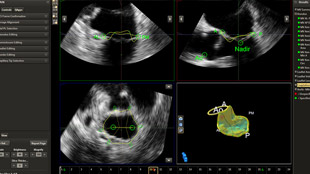

بعد تشخيص مريض بارتجاع الصمام الميترالي، ما هي خيارات العلاج المتوفرة له؟ إذا لم يكن مرشحًا للخضوع لعملية القلب المفتوح، يمكنك التفكير في معالجته عبر إصلاح الصمام الميترالي باستخدام القسطرة (TMVR). وفي يومنا الحالي، تؤمن حلول التصوير المبتكرة والأجهزة المتوفرة حديثًا خيارات جديدة لبعض المرضى.